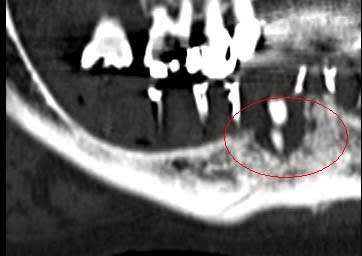

Je mets les coupes scan et tu comprendras son hésitation

Le prochain cas je propose volontiers d'être assisté par qui le veux bien, apprendre est mon plaisir, et je ne suis pas aussi buté en vrai que dans les discussions